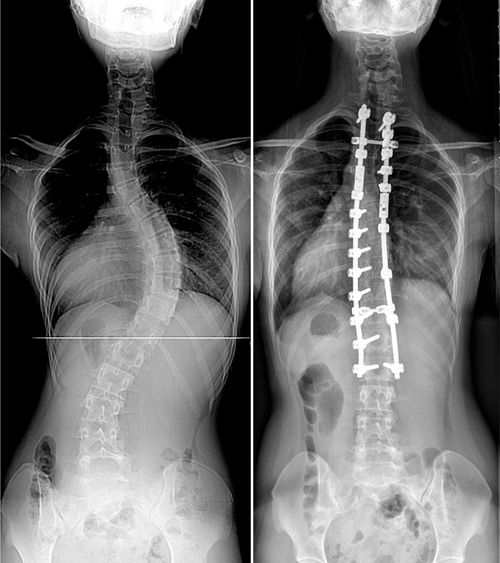

| 이중 흉추 청소년기 특발성 척추측만증 수술 전 후 수술당시 14세 여아사진으로 수술 전 상부흉추 36도, 하부흉추 62도의 측만증 소견. 수술 후 척추 측만증이 잘 교정되었고, 어깨 높이 균형도 양쪽이 대칭적으로 잘 유지 되고 있는 소견을 보이고 있다. |

인제대학교 상계백병원 척추센터 장동균 교수팀이 척추뼈가 어깨 쪽(상부 흉추)과 등 쪽(하부 흉추)에 두 번 휘어 있는 환자(이중 흉추 특발성 척추측만증) 57명을 대상으로 7년 이상 추적 관찰한 결과 수술 후 양쪽 어깨높이 균형을 잘 유지하기 위해선 상부 흉추가 경직이 있어 덜 교정되기 때문에, 상대적으로 하부 흉추를 덜 교정하는 것이 효과가 있었다고 밝혔다.

A군에서 상부 흉추는 수술 전 평균 37.5도에서 수술 후 22.4도(40.1% 교정), 최종 측정시 23.2도(37.8% 교정), 하부 흉추는 수술 전 평균 50.6도에서 수술 후 17.8도(64.2% 교정), 최종 측정시 18.2도(63.6% 교정)로 교정되었다. B군에서는 상부 흉추는 수술 전 평균 40.2도에서 수술 후 17.9도(55.4% 교정), 최종 측정시 19.9도(49.9% 교정), 하부 흉추는 수술 전 평균 56.6도에서 수술 후 16.1도(72.2% 교정), 최종 측정시 16.7도(70.9% 교정)로 교정됐다.